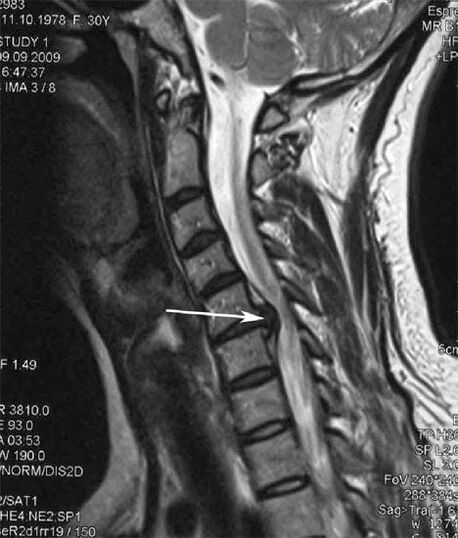

Në fazat fillestare, osteokondroza zbulohet duke përdorur MRI. Më vonë, patologjia mund të diagnostikohet duke përdorur radiografi. Në radiografitë e shtyllës kurrizore të qafës së mitrës, një ulje e distancës midis rruazave, ndryshimet patologjike në nyjet e fastës dhe osteofitoza bëhen të dukshme.